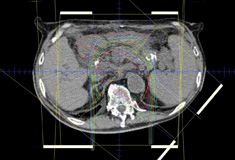

位置決めCTの画像を基本として、腫瘍の大きさや進展範囲を判断し、適切な粒子線の照射範囲や方向、線量の処方を行います。

【1】CT検査だけでは腫瘍の進展範囲がわかりにくいことがあるため、必要に応じて同じ場所のMRI画像とCT画像の重ね合わせ(フュージョン)を行います。

【2】画像をもとに腫瘍の範囲を指定し、腫瘍の形状を治療計画装置上で定義します。呼吸や体の動きによる誤差も考慮して適切な粒子線の照射野の形状を決定します。また、副作用の可能性のある臓器の指定も行います。

【3】粒子線を照射する方向やエネルギー、深さを決定します。この時に治療計画装置上で試行錯誤を繰り返し、もっとも副作用を少なくすることのできる、効果的な治療法を選びます。

【4】最後に計画情報の保存・出力を行います。

2次元線量分布図

3次元線量分布図

治療計画装置で作られた画像